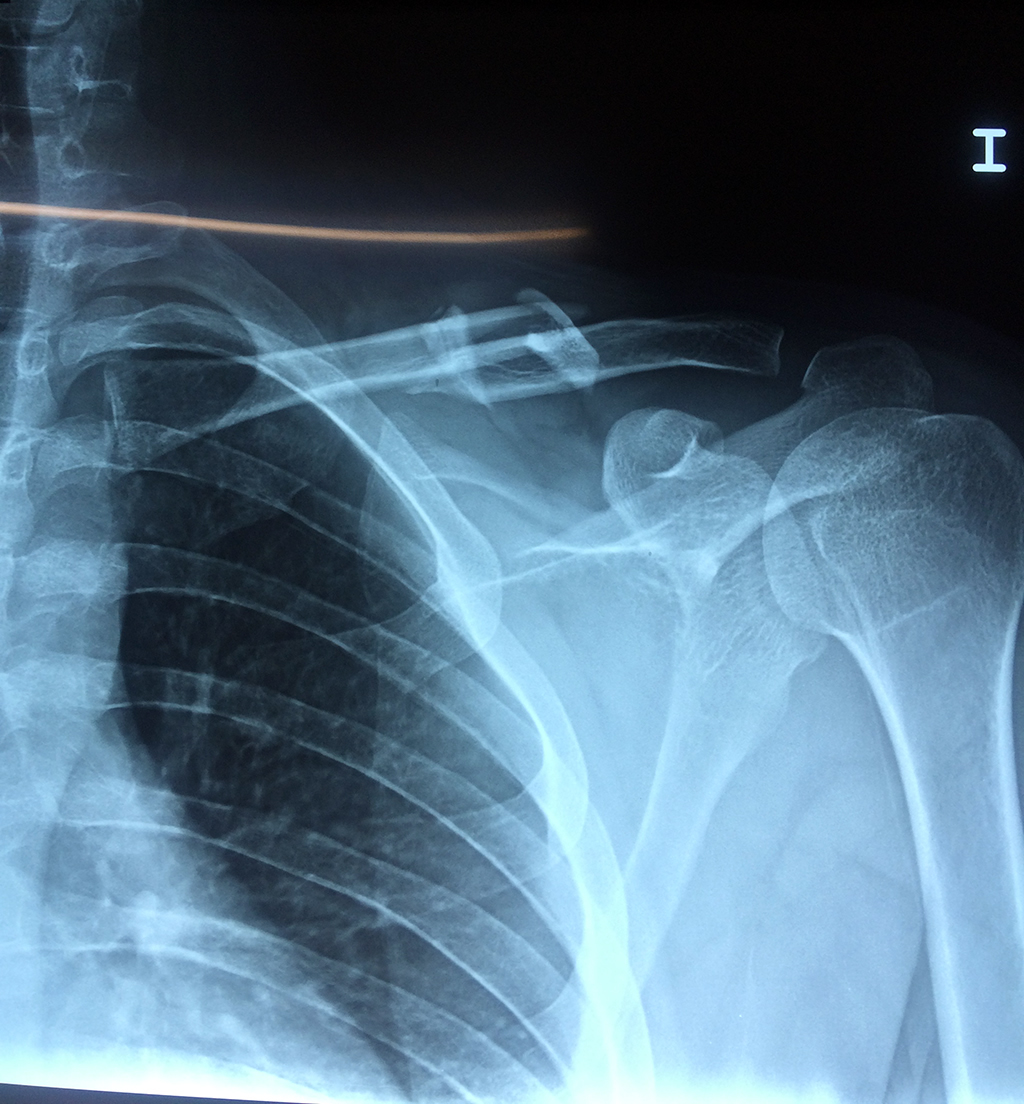

Cirugias en El Salvador - Clavícula

La clavícula es un hueso largo, con forma de "S" itálica, situado en la parte anterosuperior del tórax. Junto con la escápula forman la cintura escapular. Se puede palpar por toda su longitud y se extiende del esternón al acromion de la escápula, siguiendo una dirección oblicua lateral y posterior.